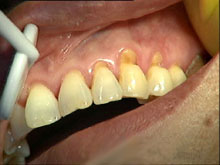

楔状缺损初期的危害表现为:在楔状缺损患者牙齿的颈部接近牙龈的部位,牙齿硬组织有少量缺损,病情逐渐加重后,便在牙颈部形成由两个平面所组成开头独特的缺损。缺损的表现光滑、坚硬而发亮、边缘整齐、牙本质暴露,有进度染有褐色,对化学温度刺激比较敏感。常伴有牙龈萎缩,牙根暴露,所以自觉牙齿变长,颜色大多为牙齿硬组织本色,呈现微黄色。楔状缺损重者可波及牙髓,造成牙髓炎、根尖炎、甚至 骨髓炎,更严重病例还会发生牙折等危害。而且随着楔状缺损患者年龄的增长,严重程度也随之加重。